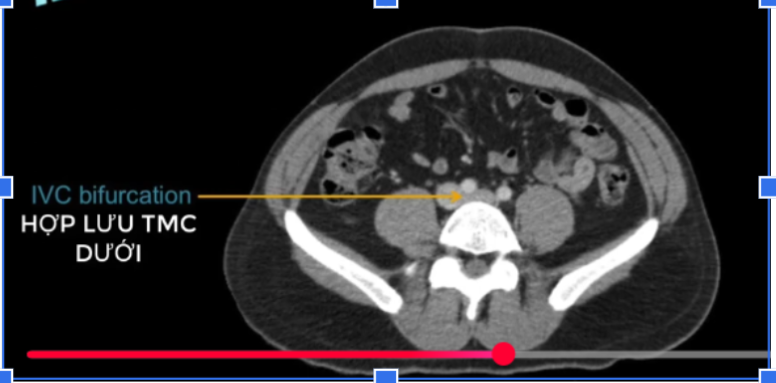

cq trong hình ?